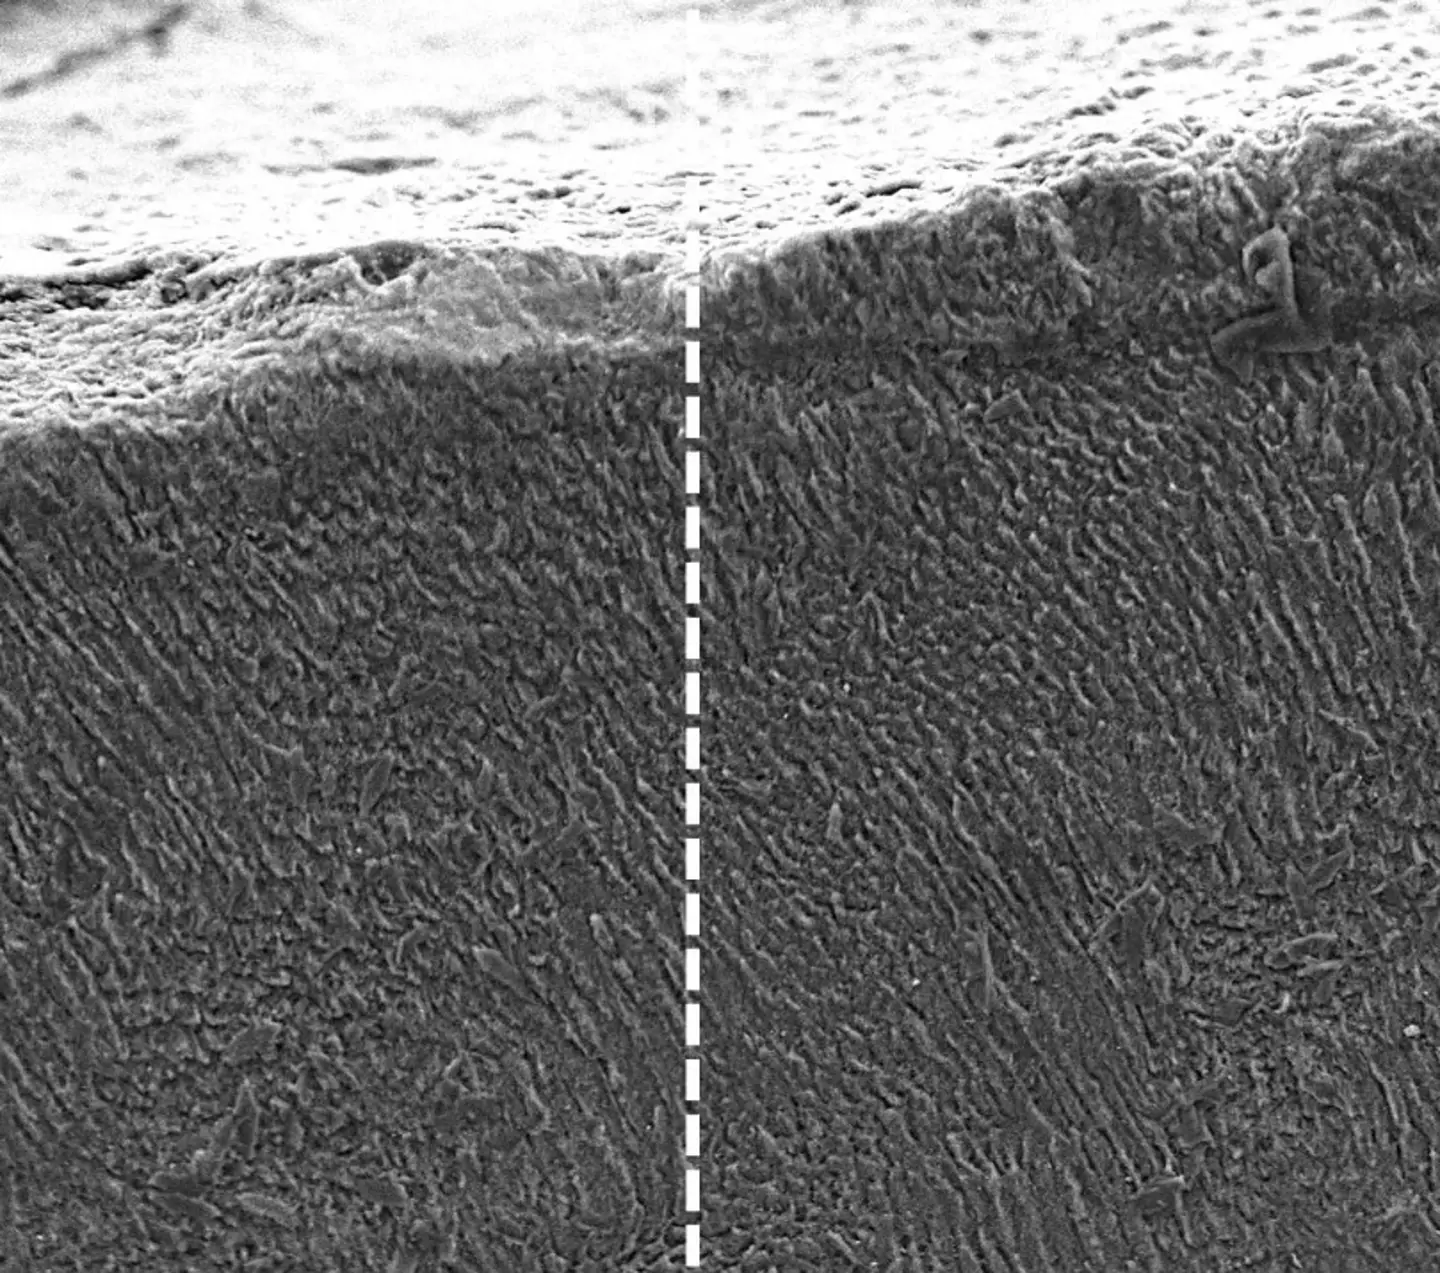

When it comes into contact with the minerals which are naturally present in our saliva, it forms a dense mineral layer which 'mimics the structure and function of natural enamel'.

Scientists extracted keratin from wool for the experiment and realised that it creates a strong, crystal-like scaffold when applied to the surface of a tooth.

Calcium and phosphate ions continue to be attracted to this as time goes on, which eventually leads to a protective enamel-like coating forming around the tooth.